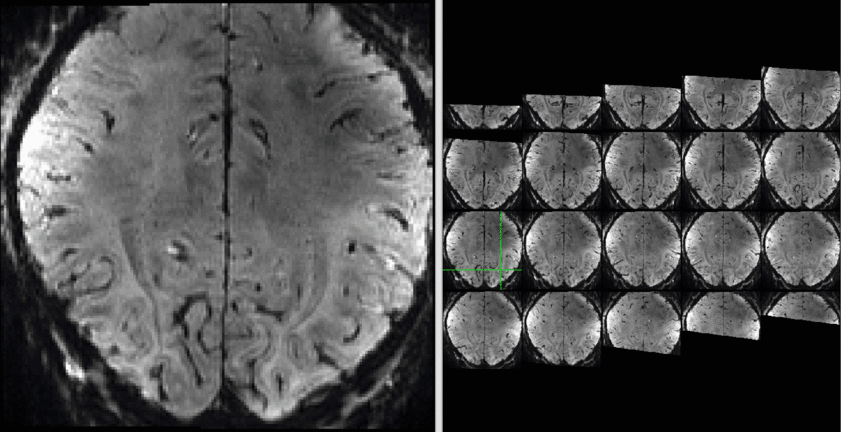

Example from Marcello Venzi acquired in Cardiff - Won Mok Shim and Insub Kim visited NIH in July 2018 to set up a high resolution VASO protocol to investigate MVPA with orientation preference. They find that orientation decoding was possible with similar accuracy in VASO and BOLD.